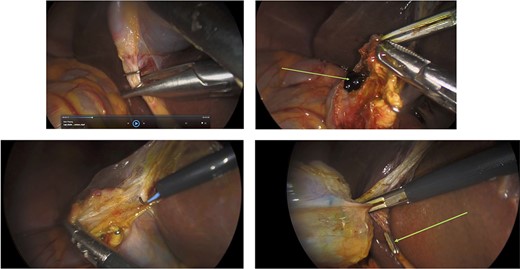

Surgery: gastric wedge resection. (a) laparoscopic entry into the lesser sac through the gastro-colonic ligament (blue arrow). (b) methylene blue markings visible on the serosal layer of the stomach (blue arrows) to delineate the tumour margins. (c) complete mobilization of the gastro-colic and gastro-splenic ligament and visualization of the gastric GIST (green arrow) on the posterior wall of the stomach. (d) macroscopically clear tumour margins post GIST resection. (e) posterior gastric wall sutured closure (yellow arrow).

An elective gastroscope showed a soft tissue mass on the posterior wall of the body of the stomach (Fig. 2a). This appeared to be an underlying submucosal tumour with no mucosal involvement. Biopsies taken showed a normal mucosa with no malignant or premalignant mucosal pathology. A complete pathological diagnosis could not be ascertained and after an extensive discussion with the patient and her family, conservative management was contemplated rather than a surgical resection. Her symptom profile did not fit clearly with either biliary colic or a gastric GIST. Three months later the patient returned to consider surgery as the pain was not subsiding. She had a second gastroscope to mark the tumour margins with methylene blue as part of her workup for a laparoscopic gastric wedge resection (Fig. 2b). The mucosa over the lesion now showed an ulceration which we ascribed to excessive tumour growth (Fig. 2c). She also requested a concomitant laparoscopic cholecystectomy as we could not clearly elucidate the aetiology behind her abdominal pain. An informed consent was signed along with permission to record the surgical procedure. The laparoscopic cholecystectomy, initially performed, was uneventful. This was a combined antero-retrograde cholecystectomy (Fig. 3a–d). The greater curvature of her stomach was mobilized laparoscopically until the lesion was clearly visualized on the posterior wall with the aid of the methylene blue dye injected at endoscopy (Fig. 4a–c). The decision was then made to convert to open surgery and the lesion excised with a 1 cm margin (Fig. 4d). The gastrotomy wound was closed in two layers with a 2–0 polydioxanone absorbable running suture (Fig. 4e). Her physiological recovery was unremarkable, and she was discharged home on post-operative Day 5. Pathology confirmed the presence of a gastric GIST with clear surgical margins. Gallbladder pathology showed a chronic cholecystitis and pigment stones (Fig. 5).